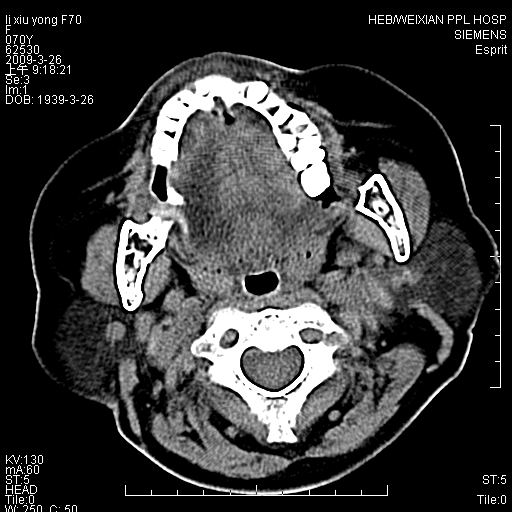

标题: CT19708:单侧上颌窦病变

老年患者,女。鼻塞多年。

考虑右侧上颌窦良性占位性病变,粘液囊肿可能性大;建议活检。

膨胀性生长,且骨质无破坏,说明时间久,良性;从密度,边缘看,内部还见坏死区,应该是实性肿瘤,定性,影像学无绝对的特异性

病灶密度很不均匀,骨壁膨胀中有断裂,考虑内翻乳头状瘤可能性大,粘液囊肿不排除

膨胀性生长,且骨质无破坏,说明时间久,良性;从密度,边缘看,内部还见坏死区,应该是实性肿瘤,定性,影像学无绝对的特异性,考虑内翻性乳头状瘤可能